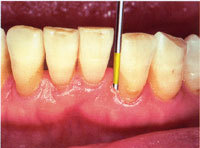

歯周ポケット検査

ごく軽い力で「プローブ」という器具を歯周ポケットに挿入します。深さを測ったり、歯や歯ぐきの内側を触って歯周病の進行程度や炎症の有無を確認します。

歯と歯ぐきの繊細な部分を調べるため、注意深く行ないますが症状によっては痛みを感じる事があります。